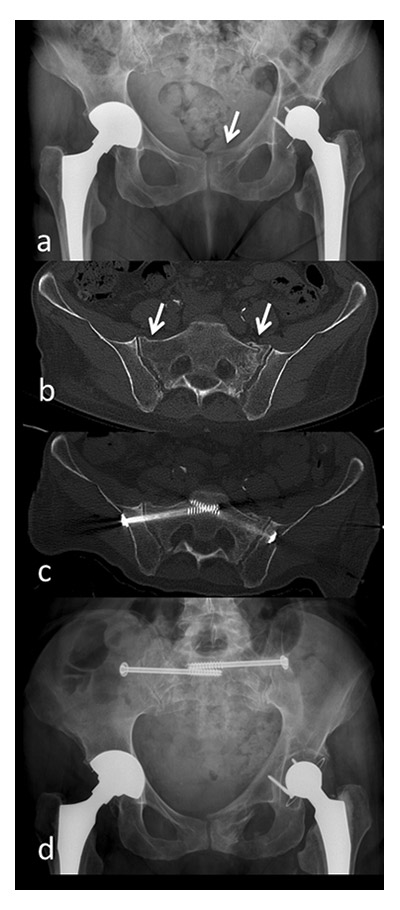

Figure 3

a) pubic ramus fracture on the left side b) CT scan six weeks after initial trauma due to increasing pain: There is a fracture of the massa lateralis on the left and a discontinuation of the cortical bone of the massa lateralis on the right c) CT-guided percutaneous screw fixation d) pelvic X-ray six weeks after surgery.

In this study all 132 patients included were primarily subject to non-operative treatment. 5 patients (4% ) showed unsuccessful evolution with persistant pain and impaired mobility 4 to 6 weeks after injury. In all these patients secondary operative treatment with osteosynthesis by percutaneous iliosacral screw fixation (all 5 cases) and additional anterior plating (2 cases) was performed (fig. 3). Nevertheless, a comparison of these 5 cases to conservatively treated patients is inappropriate due to the low number of patients operated and the fact that patients were not initially operated on. Furthermore, it was not a purpose of this study to compare conservative and surgical treatment of these injuries. Scheyerer et al. reported operative treatment in 30% of cases, whereas patients from all ages and origin of trauma (high- and low-energy) were included [30]. Alost et al. subdivided patients into those >65 years and <65 years but they did not differentiate between low- and high-energy traumas [3]. To sum up, the literature about operative treatment for geriatric pelvic ring fractures from low-energy trauma is limited. Furthermore, authors often do not distinguish between the age of the patients and the mechanism of injury making the studied patient cohorts extremely heterogenic.